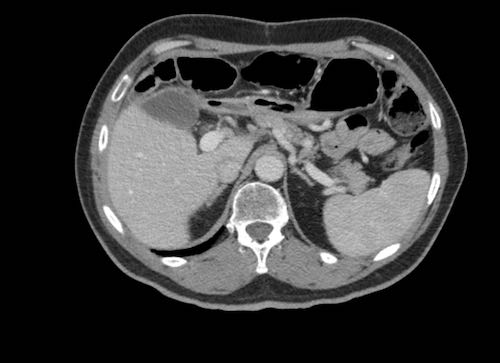

Cuộn xem ảnh CT

Ca lâm sàng 1

Cuộn qua các lát cắt.

Bạn có thể phát hiện tất cả các tổn thương cấy ghép phúc mạc không?

Bệnh nhân này đã được phẫu thuật và toàn bộ phúc mạc được ghi nhận phủ kín bởi các tổn thương u dạng kê.